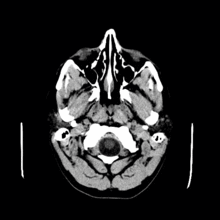

Colloid cysts can be diagnosed by symptoms presented. Additional testing will be required and the colloid cyst symptoms can resemble those of other diseases. MRI and CT scans are often used to confirm diagnosis.[4]